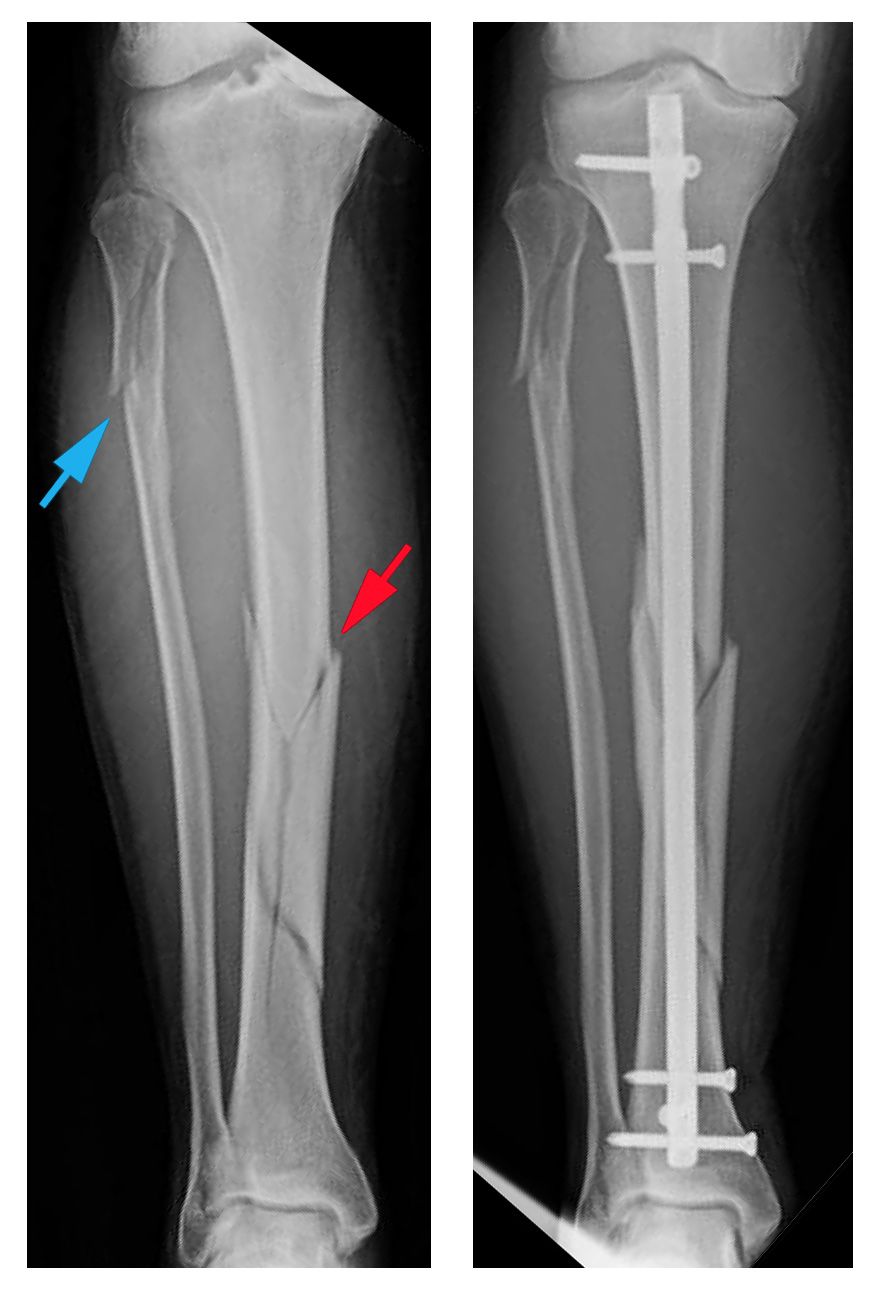

From eorif.com

Tibial Shaft Stress Fracture Images eORIF Stress Fracture Tibia Not Healing The vast majority of stress fractures will heal if treated correctly and promptly. Stress fractures take longer to heal and may require a brace, a walking boot, and crutches. Often you then see new bone growth where it has begun to heal. Learn how to prevent and treat them. Stress fractures are tiny cracks in bones often caused by overuse. Stress Fracture Tibia Not Healing.